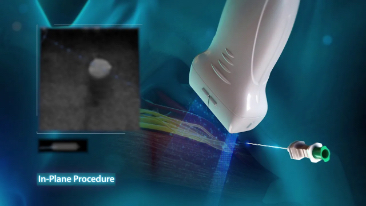

With its superior image quality, simple touchscreen operation and class-leading intelligent tools, the Mindray TE7 ACE is designed to simplify and speed-up ultrasound examinations.

Its versatility makes it suitable for demanding point-of-care environments including Critical Care, Emergency and Anaesthetics.

Images